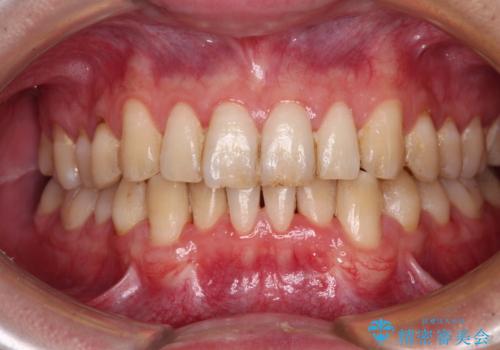

歯肉移植により根面被覆が達成されるとともに、歯肉が厚みを増したことで、今後の歯肉退縮リスクを軽減させることができました。